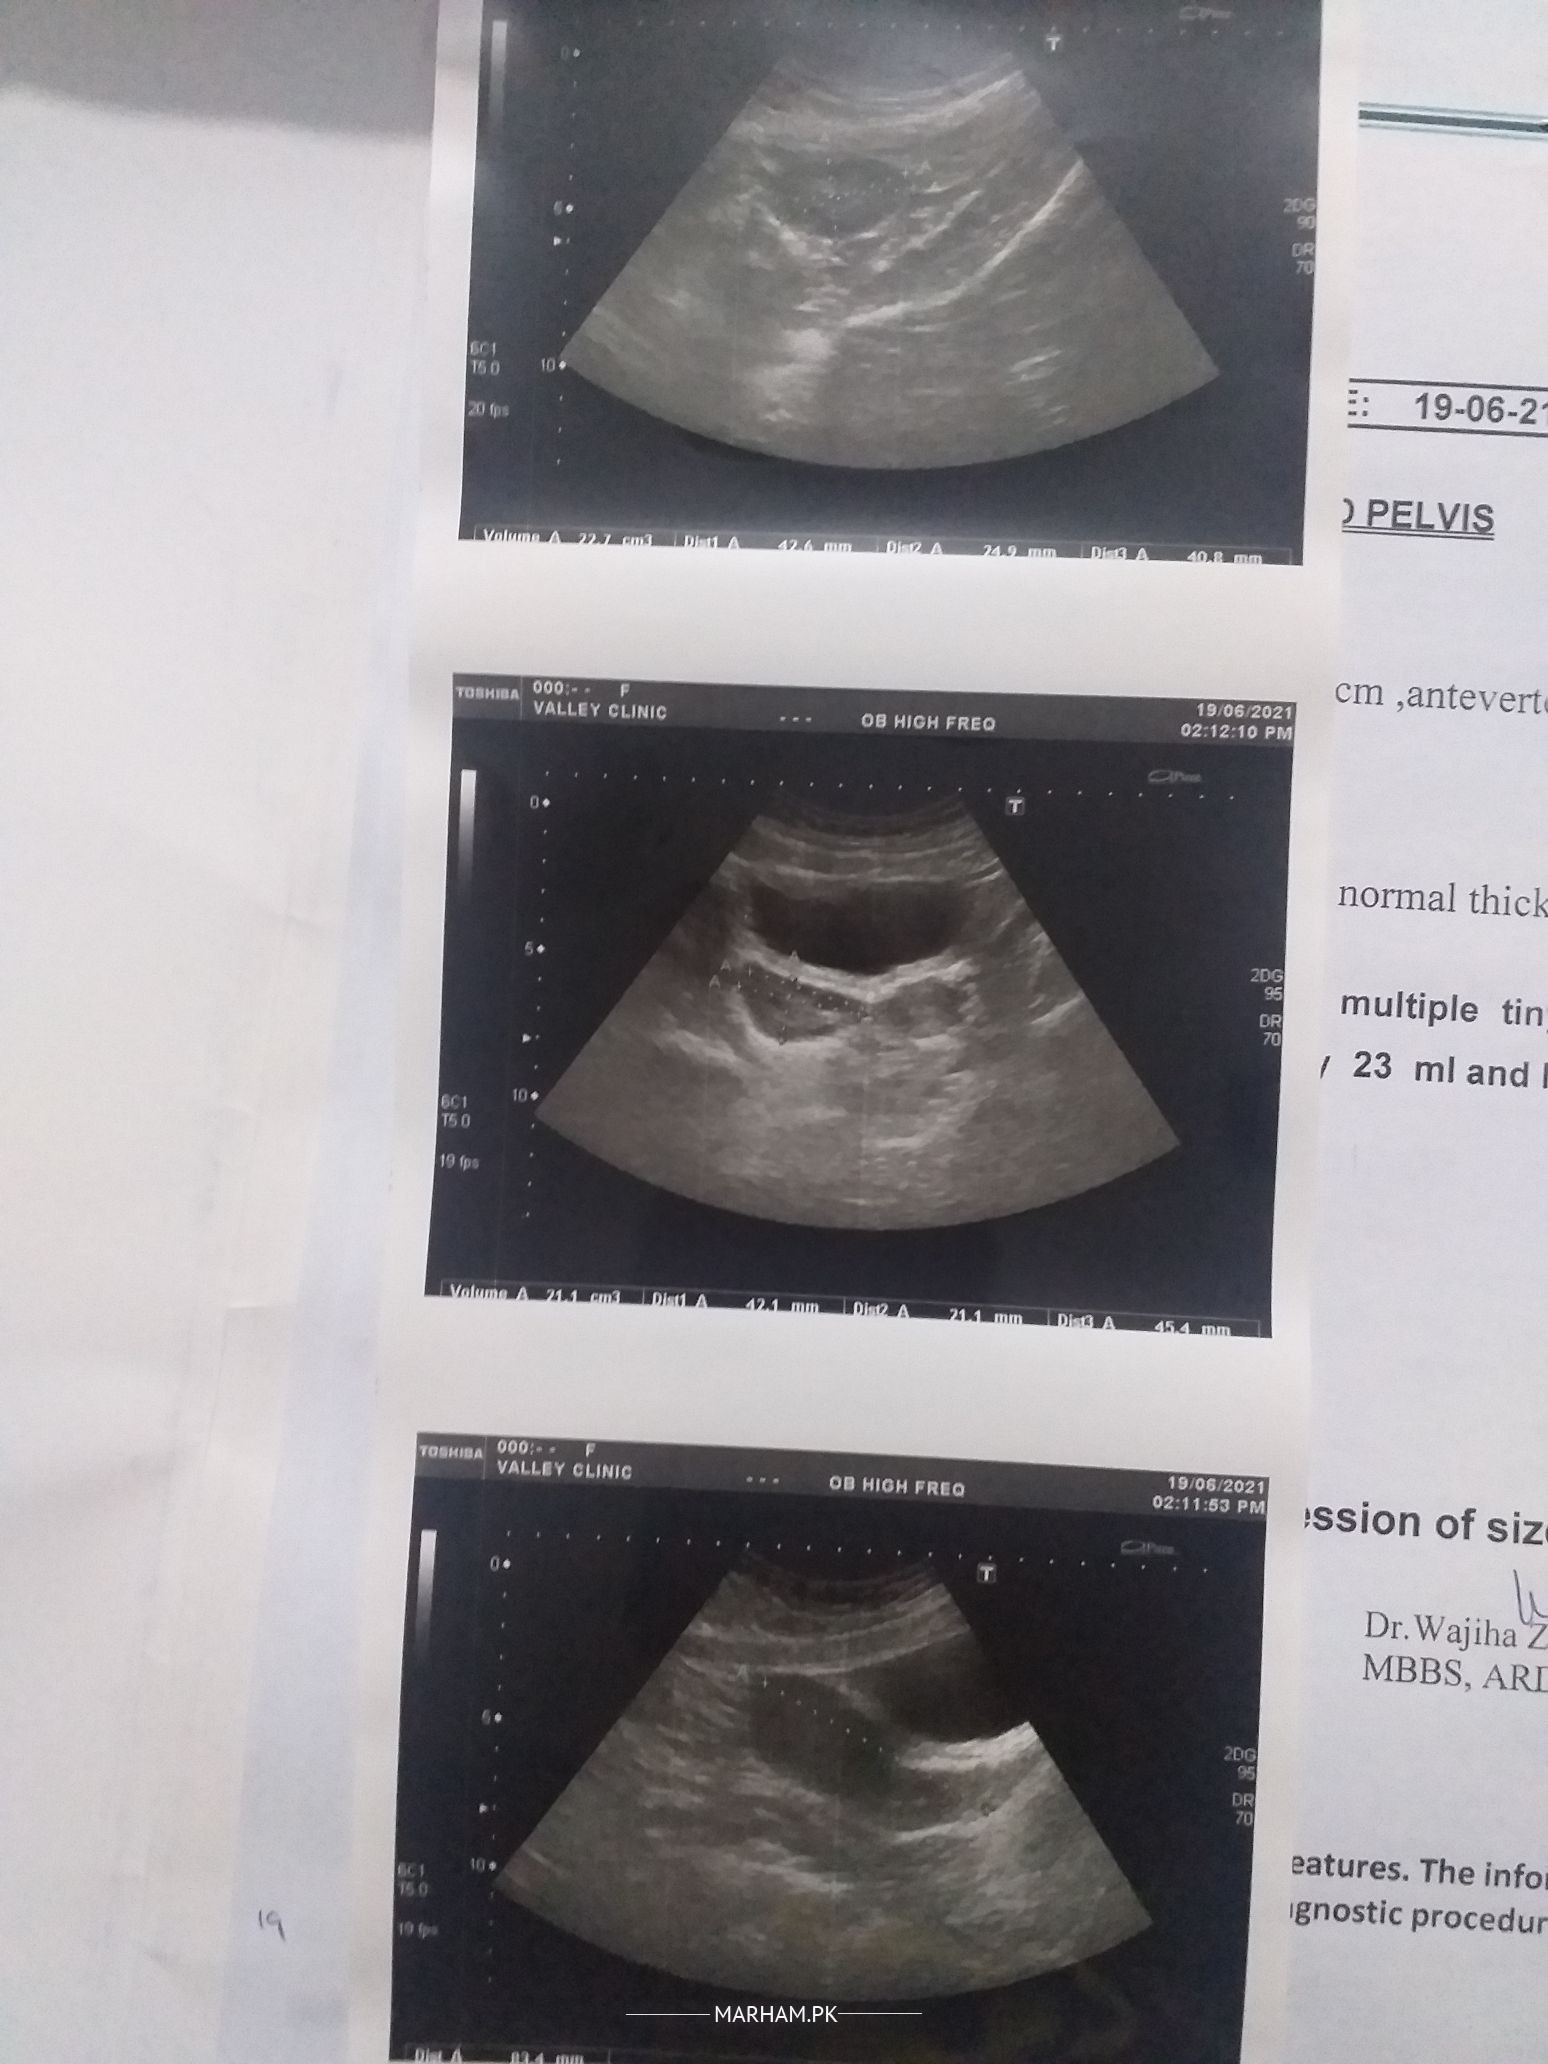

I took this ultrasound test on June 19, 2021. Can any gynaecologist please tell me the exact situation of the cysts on my ovaries? I have been concluded to have polycystic ovaries. Thank you very much.

When no dominant/ growing follicle seen in either ovary on 12-14 th day of periods or someone follicle doesn’t matures ( 18-22mm) during whole cycle , such ovaries r known as polycystic. It’s reason should be ruled out and treated.

You have polycystic ovarian syndrome. It’s a condition of ovaries that disrupt your periods. Please visit a gynaecologist for need of medical treatment for this.